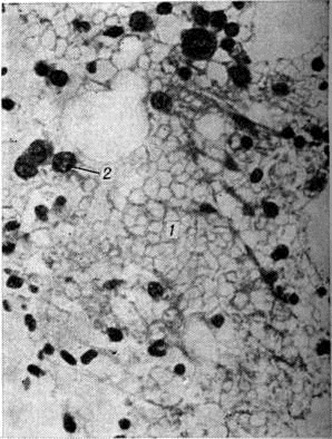

Рис. 2. Микропрепарат ткани селезёнки при остром монобластном лейкозе: видна лейкозная инфильтрация (1), резкое уменьшение размеров фолликула (2). Окраска гематоксилин-эозином; × 280.

Лейкозная инфильтрация ткани селезёнки и лимфатических, узлов сопровождается уменьшением размеров (рисунок 2) и числа фолликулов вплоть до полного их исчезновения. В селезёнке часто наблюдается инфильтрация трабекул с разволокнением стенок трабекулярных сосудов, с деформацией и сужением их просвета, имеются поля кровоизлияний. В лимфатических, узлах вначале возникают очаговые инфильтраты, которые по мере прогрессирования болезни увеличиваются в размерах, и поражение становится диффузным.